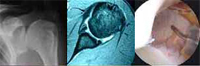

Anatomy of the Shoulder

The shoulder joint is formed by the proximal humerus, scapula and clavicle. It is divided into two articular spaces, the subacromial space and the glenohumeral joint. These two spaces are separated by the rotator cuff tendons.

Shoulder muscles, especially the deltoid and the rotator cuff muscles (supraespinatus, infraespinatus and subescapularis) provide strength and joint movement.

The Glenohumeral ligaments are part of the capsular complex and act as a reinforcements to avoid joint dislocation.